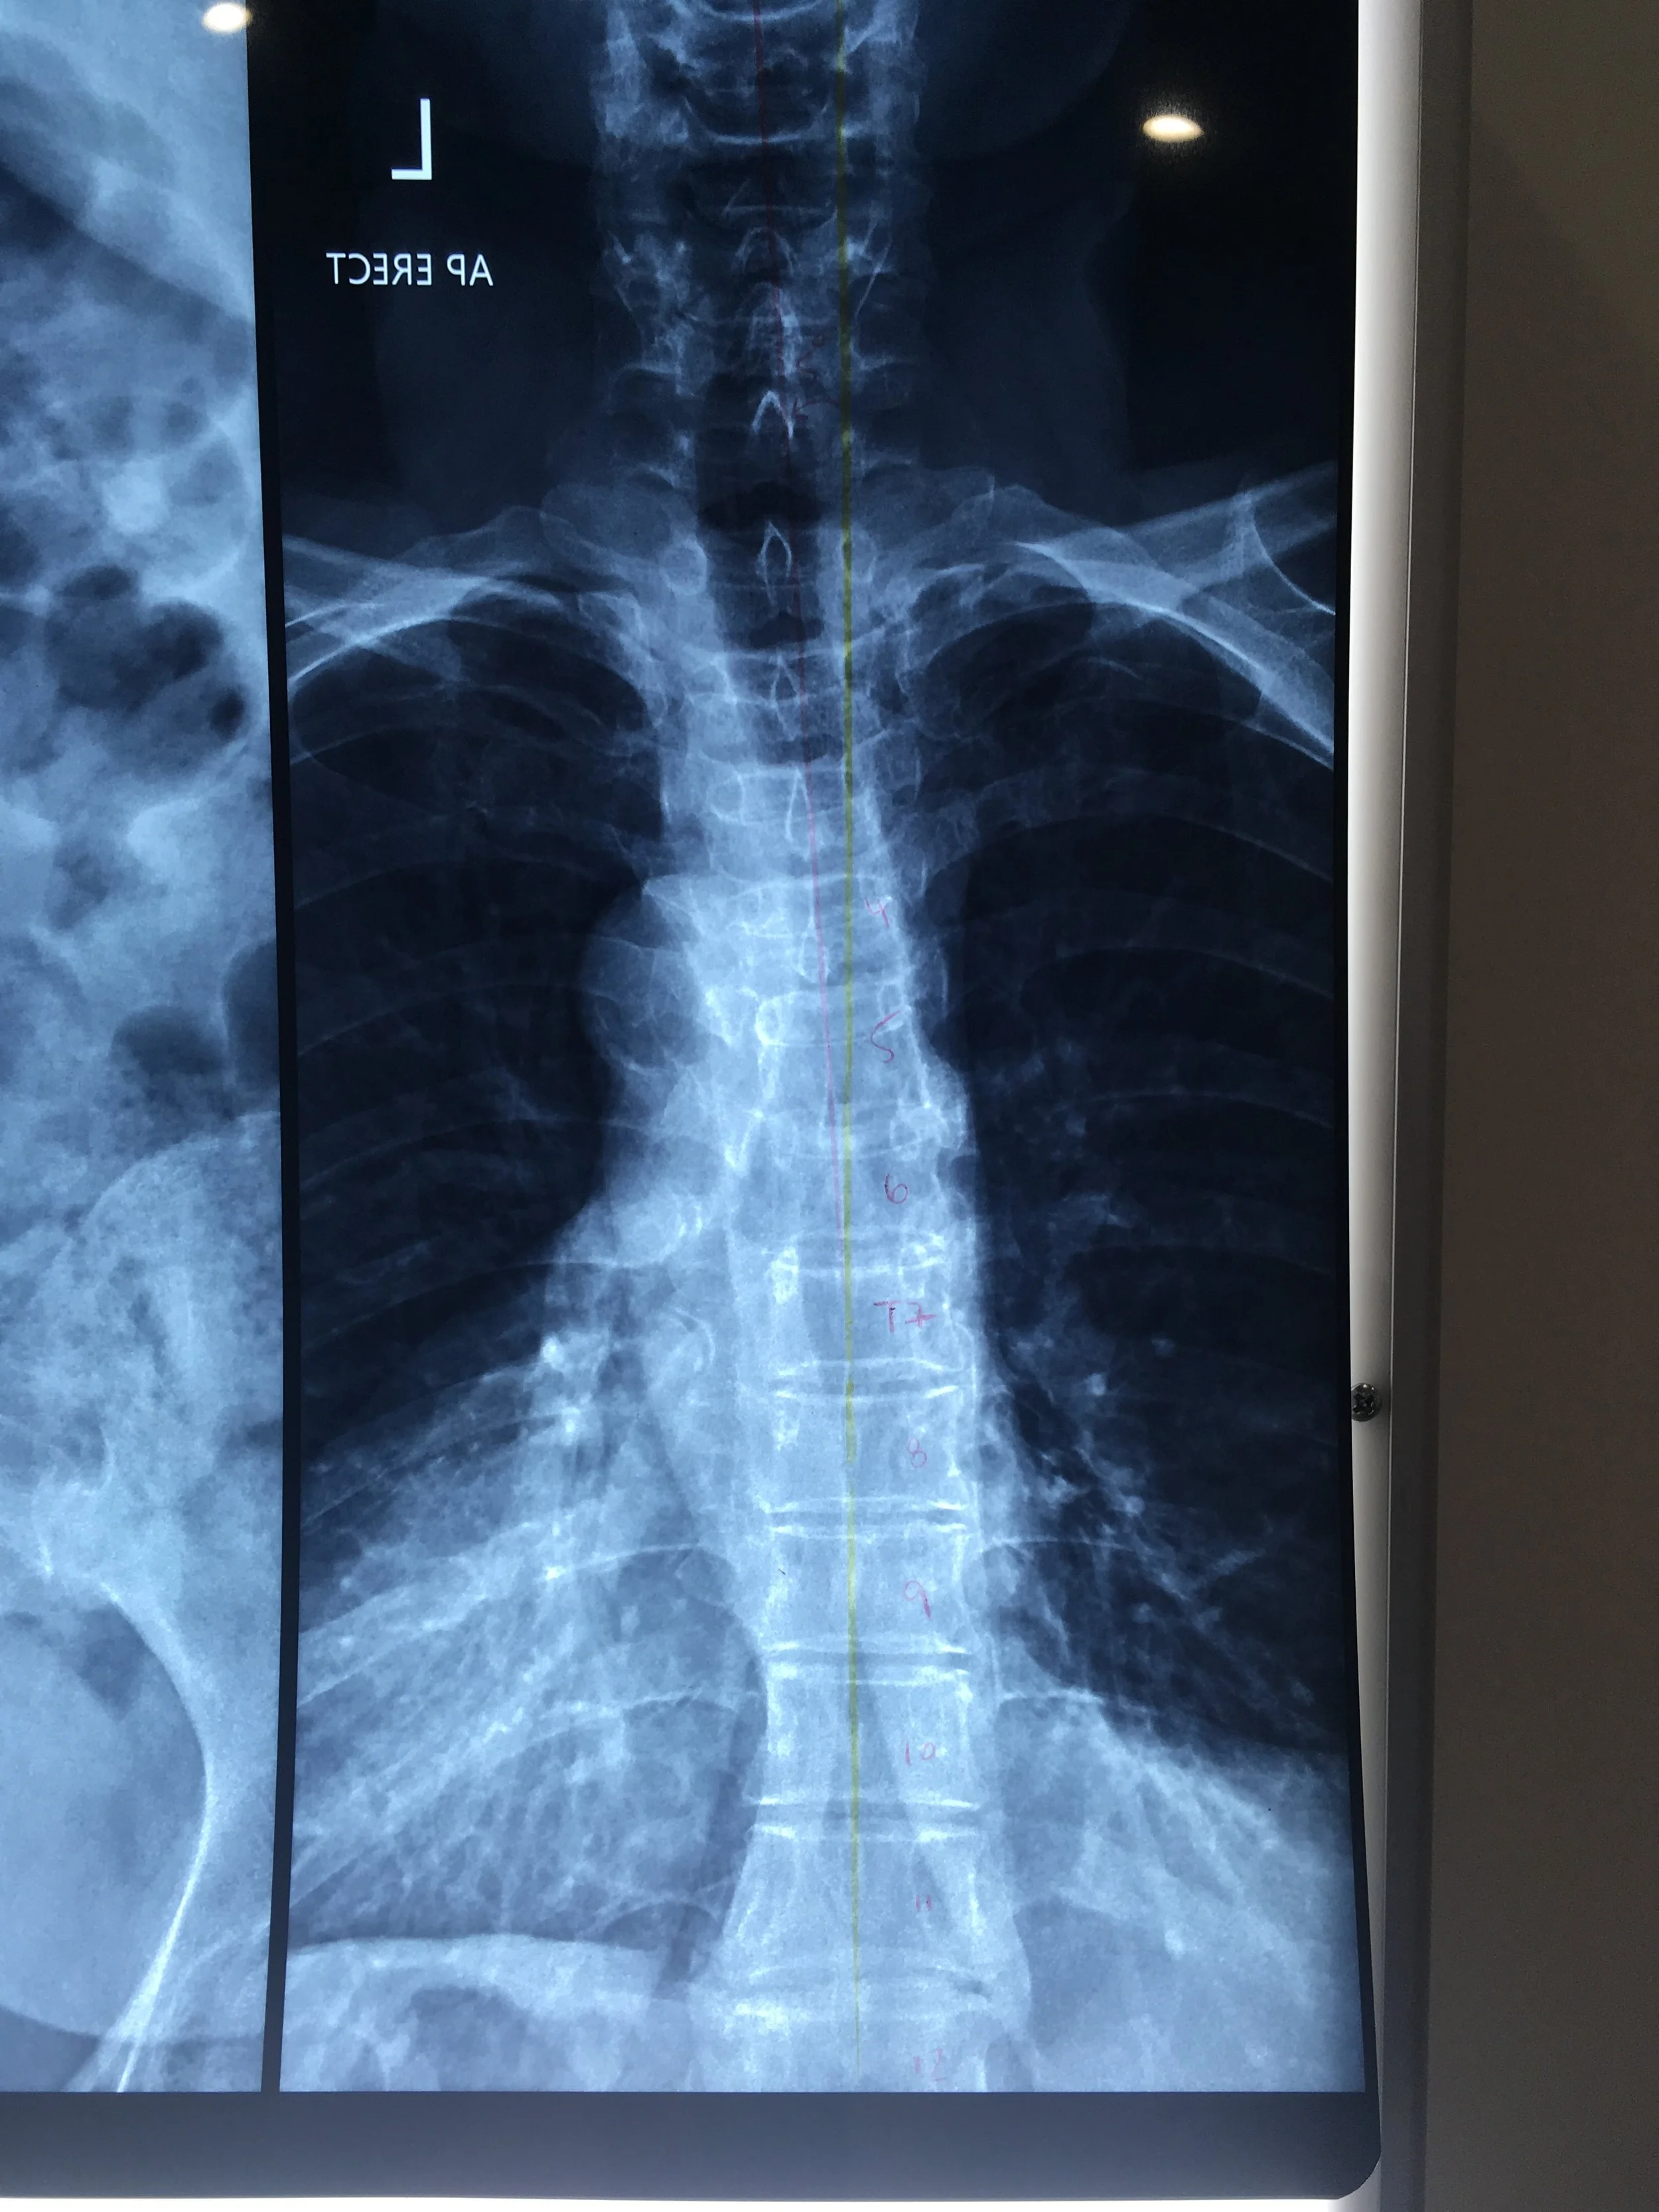

• Scoliosis is defined as the lateral curve of the spine. This means the curvature of a spine as you are looking at someone from behind. Scoliosis often has an associated rotational component which means the vertebrae may have turned & appear more prominent on one side versus the other.

As Chiropractors, we often obtain an x-ray or EOS scan of your spine in order to calculate the degree & angle of your spine, as well as help determine the cause of your scoliosis if not idiopathic.

• Scoliosis is considered of concern when it has an angle greater than 10 degrees.

• Not always. In many cases, we can assess posture, movement, and alignment without X-rays. If your curve is significant, or if you are a growing teenager, we may recommend an X-ray to measure and track changes over time. We’ll always discuss this with you before proceeding.